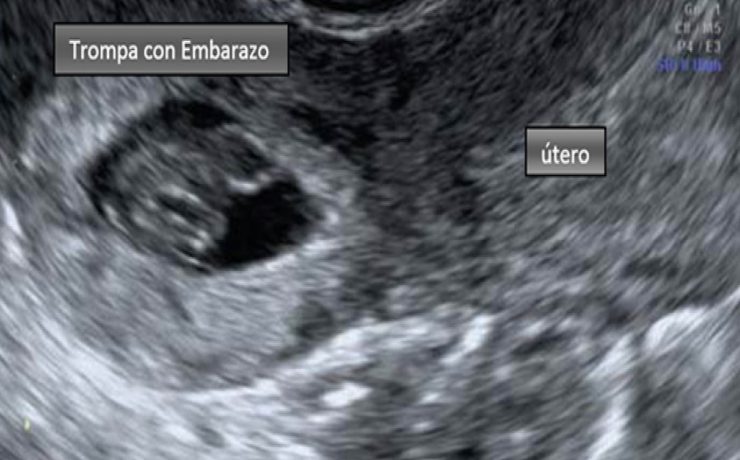

La incidencia de coledocolitiasis después de la intervención quirúrgica tiene una incidencia del 10 porciento, Los cálculos pueden permanecer por años dentro de la vía extra hepática y no manifestar síntomas. Los cálculos pequeños pueden pasar por el colédoco y el duodeno sin producir síntomas (menores 3mm), solo que se